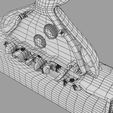

神经肌肉接头示意图